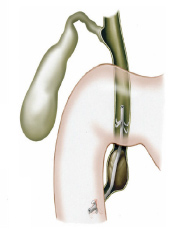

Pacientes que têm o objetivo de emagrecer, podem ter como alternativa a passagem de um balão intragástrico. A passagem do balão é realizada por endoscopia e o procedimento dura cerca de 20 a 30 minutos.

Passagem de Balão Intragástrico

1. O balão intragástrico é introduzido desinsuflado durante a endoscopia e colocado no estômago.

2. Um líquido azul (azul de metileno diluído em soro fisiológico) é colocado dentro do balão através de uma válvula. O volume varia entre 500-700 ml.

3. O aparelho de endoscopia é removido e o balão intragástrico pode ser deixado por um período de até 6 meses.

Como funciona o balão intragástrico?

O balão intragástrico ocupa um espaço dentro do estômago e o paciente fica com sensação de plenitude e saciedade precoce. Em outras palavras, sobra menos espaço para os alimentos, diminuindo o volume ingerido nas refeições.

Pacientes que têm o objetivo de emagrecer, podem ter como alternativa a passagem de um balão intragástrico. A passagem do balão é realizada por endoscopia e o procedimento dura cerca de 20 a 30 minutos.

Passagem de Balão Intragástrico

1. O balão intragástrico é introduzido desinsuflado durante a endoscopia e colocado no estômago.

2. Um líquido azul (azul de metileno diluído em soro fisiológico) é colocado dentro do balão através de uma válvula. O volume varia entre 500-700 ml.

3. O aparelho de endoscopia é removido e o balão intragástrico pode ser deixado por um período de até 6 meses.

Como funciona o balão intragástrico?

O balão intragástrico ocupa um espaço dentro do estômago e o paciente fica com sensação de plenitude e saciedade precoce. Em outras palavras, sobra menos espaço para os alimentos, diminuindo o volume ingerido nas refeições.